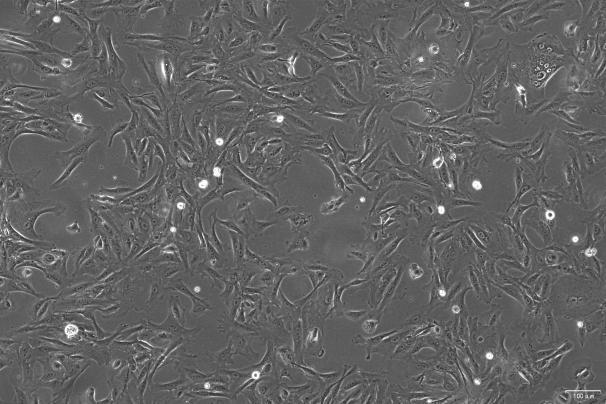

OriCell®UM-UC-3 人膀胱移行细胞癌细胞系

人膀胱移行细胞癌细胞(UM-UC-3)是一种从男性患者膀胱中分离出来的上皮样细胞,从膀胱移行细胞癌中分离出来,这是一种超三倍体人类细胞系。模态染色体数为 80,发生在 42%的细胞中。具有 78 条 染色体的细胞也以高频率发生。具有较高倍性的细胞率为 2.5%。每个细胞中有 30 条或更多的标记染色体。

贴壁生长;上皮细胞样 |